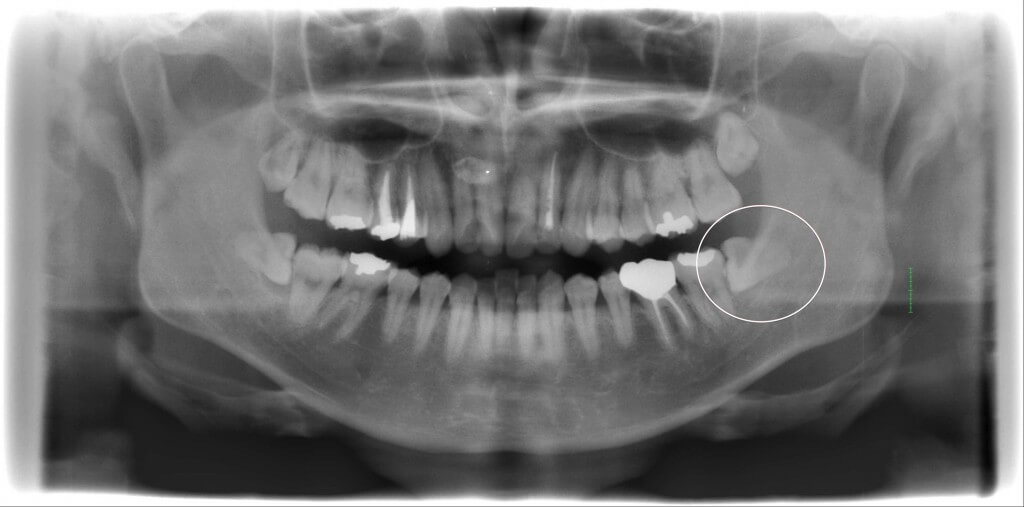

埋伏歯抜歯

Case.1

CT検査にて左右に下顎水平埋伏智歯が認められます。下歯槽管との関係を確認した上で歯牙を分割抜歯いたしました。 最小限の侵襲で処置を行う事により腫脹、疼痛も最小限で抑えられます。